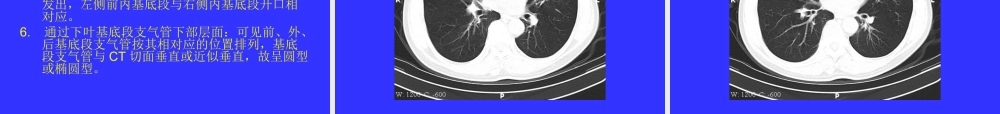

如何阅读胸部CT片一、胸部CT技术参数应用胸部CT扫描一般取仰卧位,于憋气状态下进行扫描,常规从肺尖扫至肋膈角。胸部由含气的肺组织、软组织及骨骼组成,观察这些不同密度的组织需选择不同的窗宽与窗位,一般观察纵膈和胸部软组织窗宽为400~500HU,窗位为0~50HU,观察肺,窗宽为1000~2000HU,窗位为-600~-800HU。连续横断面扫描可以重建成冠状位、矢状位及三维重建,这对于观察复杂解剖部位有极大的帮助,图像重建的质量取决于横断面扫描的厚度,层厚越薄,间隔越小,图像质量越好。•二、造影剂增强扫描•胸部含有大量气体,病灶一般为软组织,与含气的肺组织有较大的密度差异。纵膈内有丰富的低密度脂肪,故纵膈内解剖结构很清楚,一般不做造影增强,但以下情况需做增强扫描:1.病人消瘦,纵膈内缺乏脂肪;2.有血管畸形及血管病变;3.鉴别纵膈的淋巴结核与恶性肿瘤;4.明确肺和纵膈肿瘤对血管是否侵犯以及受侵程度;5.观察病变的增强特点,对炎症、良性肿瘤及恶性肿瘤作出鉴别。注射造影剂方法以一次大剂量静脉注射效果最佳。扫描方法为在常规扫描基础上确定重点扫描区。•三、正常纵膈解剖•选出具有代表性的层面加以分析,并以层面中具有特征性的解剖结构命名。1.胸骨切迹或胸锁关节层面:该层面可见到三对血管排列在气管两侧,靠前、靠外是一对左右头臂静脉,靠后是一对锁骨下动脉,紧贴气管两侧为左右颈总动脉。2.主动脉弓上层面:此层面可见五支血管影,左右头臂静脉,头臂干,左颈总动脉,左锁骨下动脉。右头臂干左食管右颈总动脉左颈总动脉右锁骨下动脉左锁骨下动脉3.主动脉弓层面:主动脉弓自右前向左后斜行,老年人由于动脉硬化,主动脉弓可不呈水平走行,此层面可见胸腺,呈三角形,尖端指向前。4.主肺动脉窗层面:上界为主动脉弓下缘,下界为左肺动脉,前方为升主动脉,后方为气管,在同一层面,升主动脉总是大于降主动脉。5.左肺动脉层面:为主肺动脉窗下界,主肺动脉后延伸为左肺动脉。6.主肺动脉与右肺动脉层面:右肺动脉从主肺动脉发出向后、向右延伸,位于腔静脉后方、中间段支气管前方,右肺动脉管径不超过25mm,肺动脉主干不超过29mm。7.左心房层面:左心房前方为主动脉根部和右心耳,后方为食道、奇静脉、降主动脉。8.四腔心层面:此层面可见右心房、室,左心房、室,心腔与心壁不注射造影剂无法区别。9.纵膈内其它几个重要脏器,气管、食管(一般壁厚不超过3mm)、胸腺(位于血管前间隙,分左右两叶,于幼儿时期较大,以后...